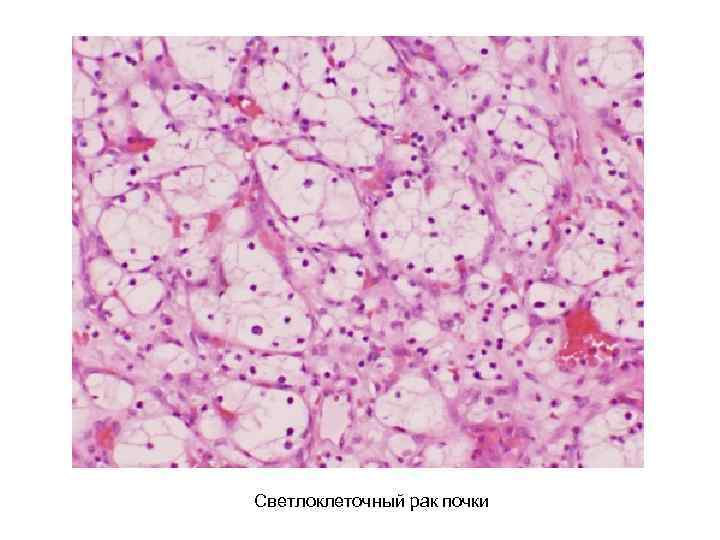

Фотографии опухоли медуллярной аденокарциномы